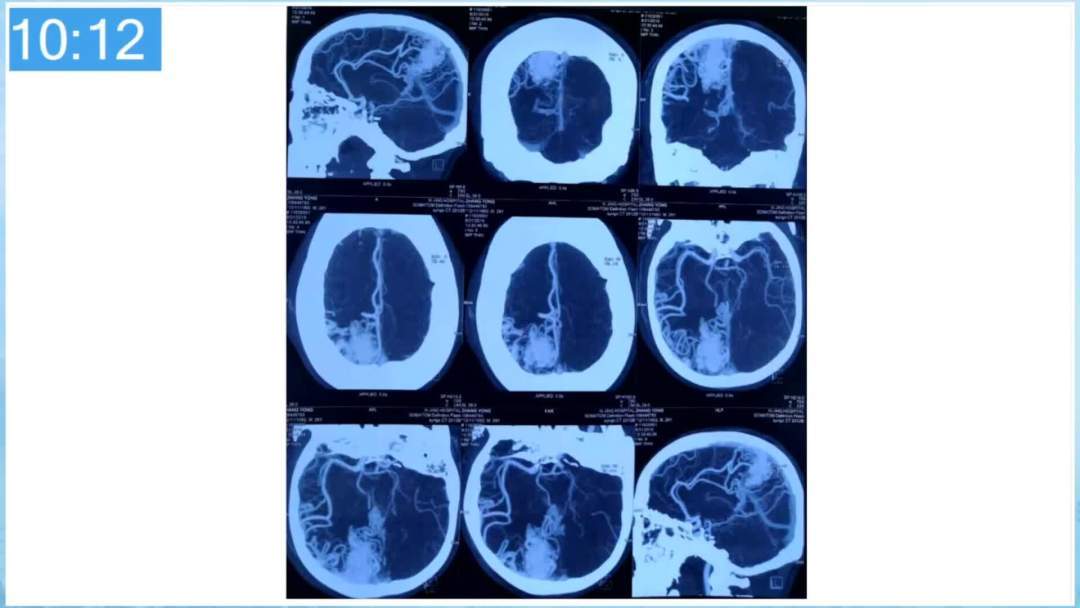

合理的复合平台下的综合治疗,针对每一个病变对应不同方法安全性分析,不预设、不排斥,每种技术发挥到最佳,互相保障。

本期为大家特别分享:空军军医大学唐都医院邓剑平教授的精彩会议内容《颅内动静脉畸形的复合手术治疗》,欢迎大家阅读和分享!